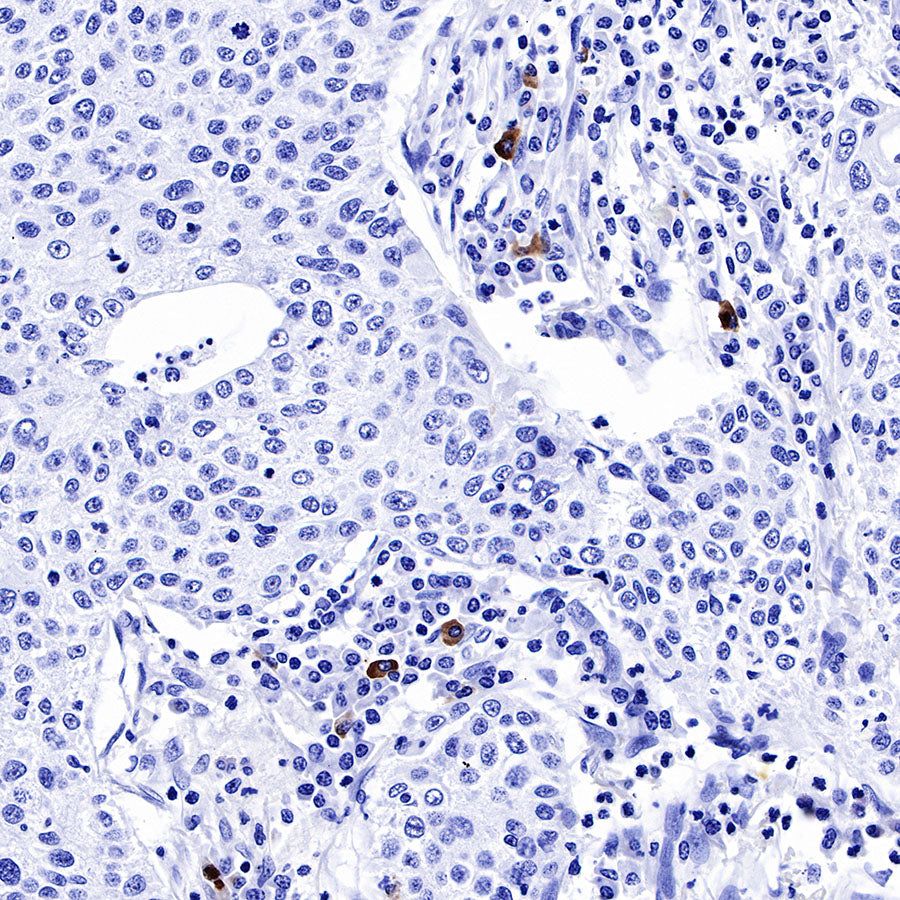

IHC shows positive staining in paraffin-embedded human spleen. Anti-IGJ antibody was used at 1/1600 dilution, followed by a HRP Polymer for Mouse & Rabbit IgG (ready to use). Counterstained with hematoxylin. Heat mediated antigen retrieval with Tris/EDTA buffer pH9.0 was performed before commencing with IHC staining protocol.